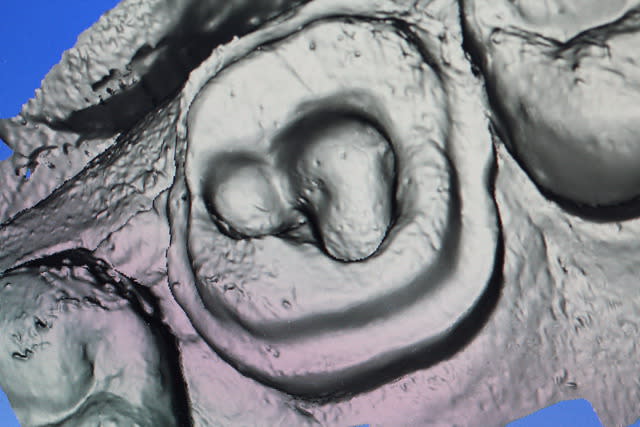

un cas réalisé depuis : une endocouronne réalisée la semaine dernière sur une nécrose d'origine paro ,

surfaçage + laser pendant la cuisson , a voir dans le temps...

C'est un joli cas mais ce n'est pas une endocouronne , c'est une couronne-endo très différent du point de vue comportement mécanique. Il aurait été possible d'être moins agressif en faisant une endo-V-Prep.